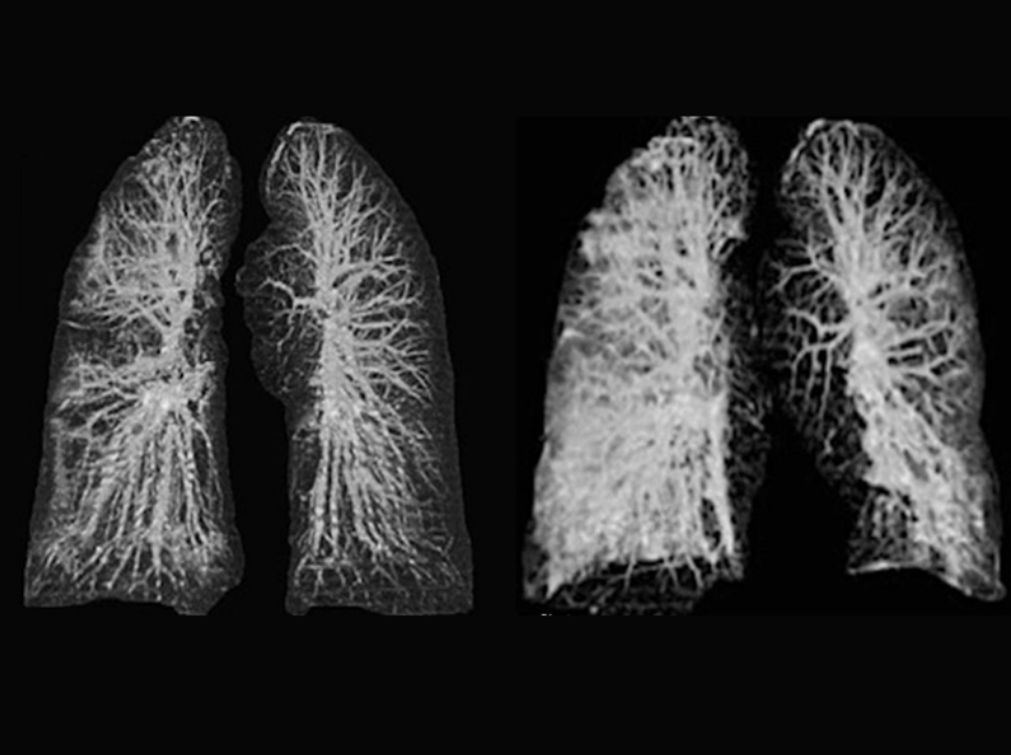

根据Mail Onlin的报道,新冠肺炎对于患者肺的影响非常之大,通过X光我们甚至发现一些令人震惊的现象。

X光片中的肺是来自欧洲首两宗确诊个案,也就是一对来自中国湖北武汉的夫妇。该对武汉夫妇分别为67岁男士及65岁女士。据悉,今年1月份在意大利旅游时他们感到身体不适,随后在罗马确诊感染新冠病毒。

二人肺部的X光片近日曝光,可见肺部出现磨砂玻璃状影像(ground-glass opacities),整个肺部都受到了严重的影响。

据报,二人确诊后,罗马国家传染病研究所(National Institute of Infectious Diseases)的人员进行研究。研究人员指,二人发烧并出现呼吸困难的情况后,接受测试后,证实感染新冠肺炎,及后发展成急性呼吸窘迫症候群(ARDS)。确诊4日后呼吸衰竭,确诊6日后只能依赖呼吸机维生。